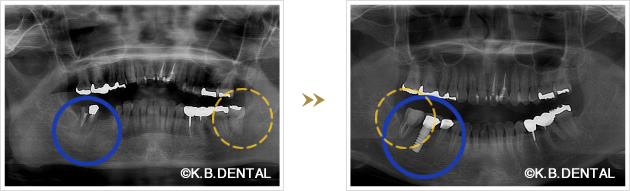

親知らずの移植症例

当院では、親知らずを他の場所の奥歯に移植するケースも数多く行っております。奥歯の移植治療を考えられている方は、一度ご相談ください。

下顎インプラント埋入と歯牙移植を同時に行なったケース